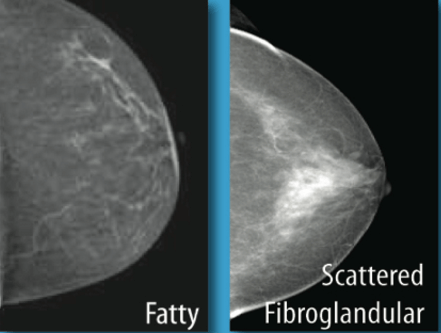

Pic01: Fibrograndular Densities in breast

Fibroglandular densities are derivations of imaging particulars that provide estimate of fibrous connections and glandular measures in particular body part, However when it comes to Breast, how much of your breast tissue is made of fibrous connective tissue and glandular tissue is an important yardstick to know your risks or complications. If you have more fibrous and glandular tissues then your type of breast tissue are considered to be dense. Glandular tissues are related to milk glads.  Radio-diagnosis through Mammograms makes it challenging to penetrate through dense breast tissues and see chances of carcinogenic developments in the healthy tissues, compared with those who have lesser fibroglandular densities. While Fatty tissue appears dark or see-through on a mammogram, making it easier to spot white areas indicating cancer.

If you have A or B score, it means you have least dense tissues more fatty tissues. There are generally 10% of women fall in A and 40% in B  category. B category is also known as scattered fibroglandular densities. Genetics, Age and size of breast can be some reasons to fall in this category.